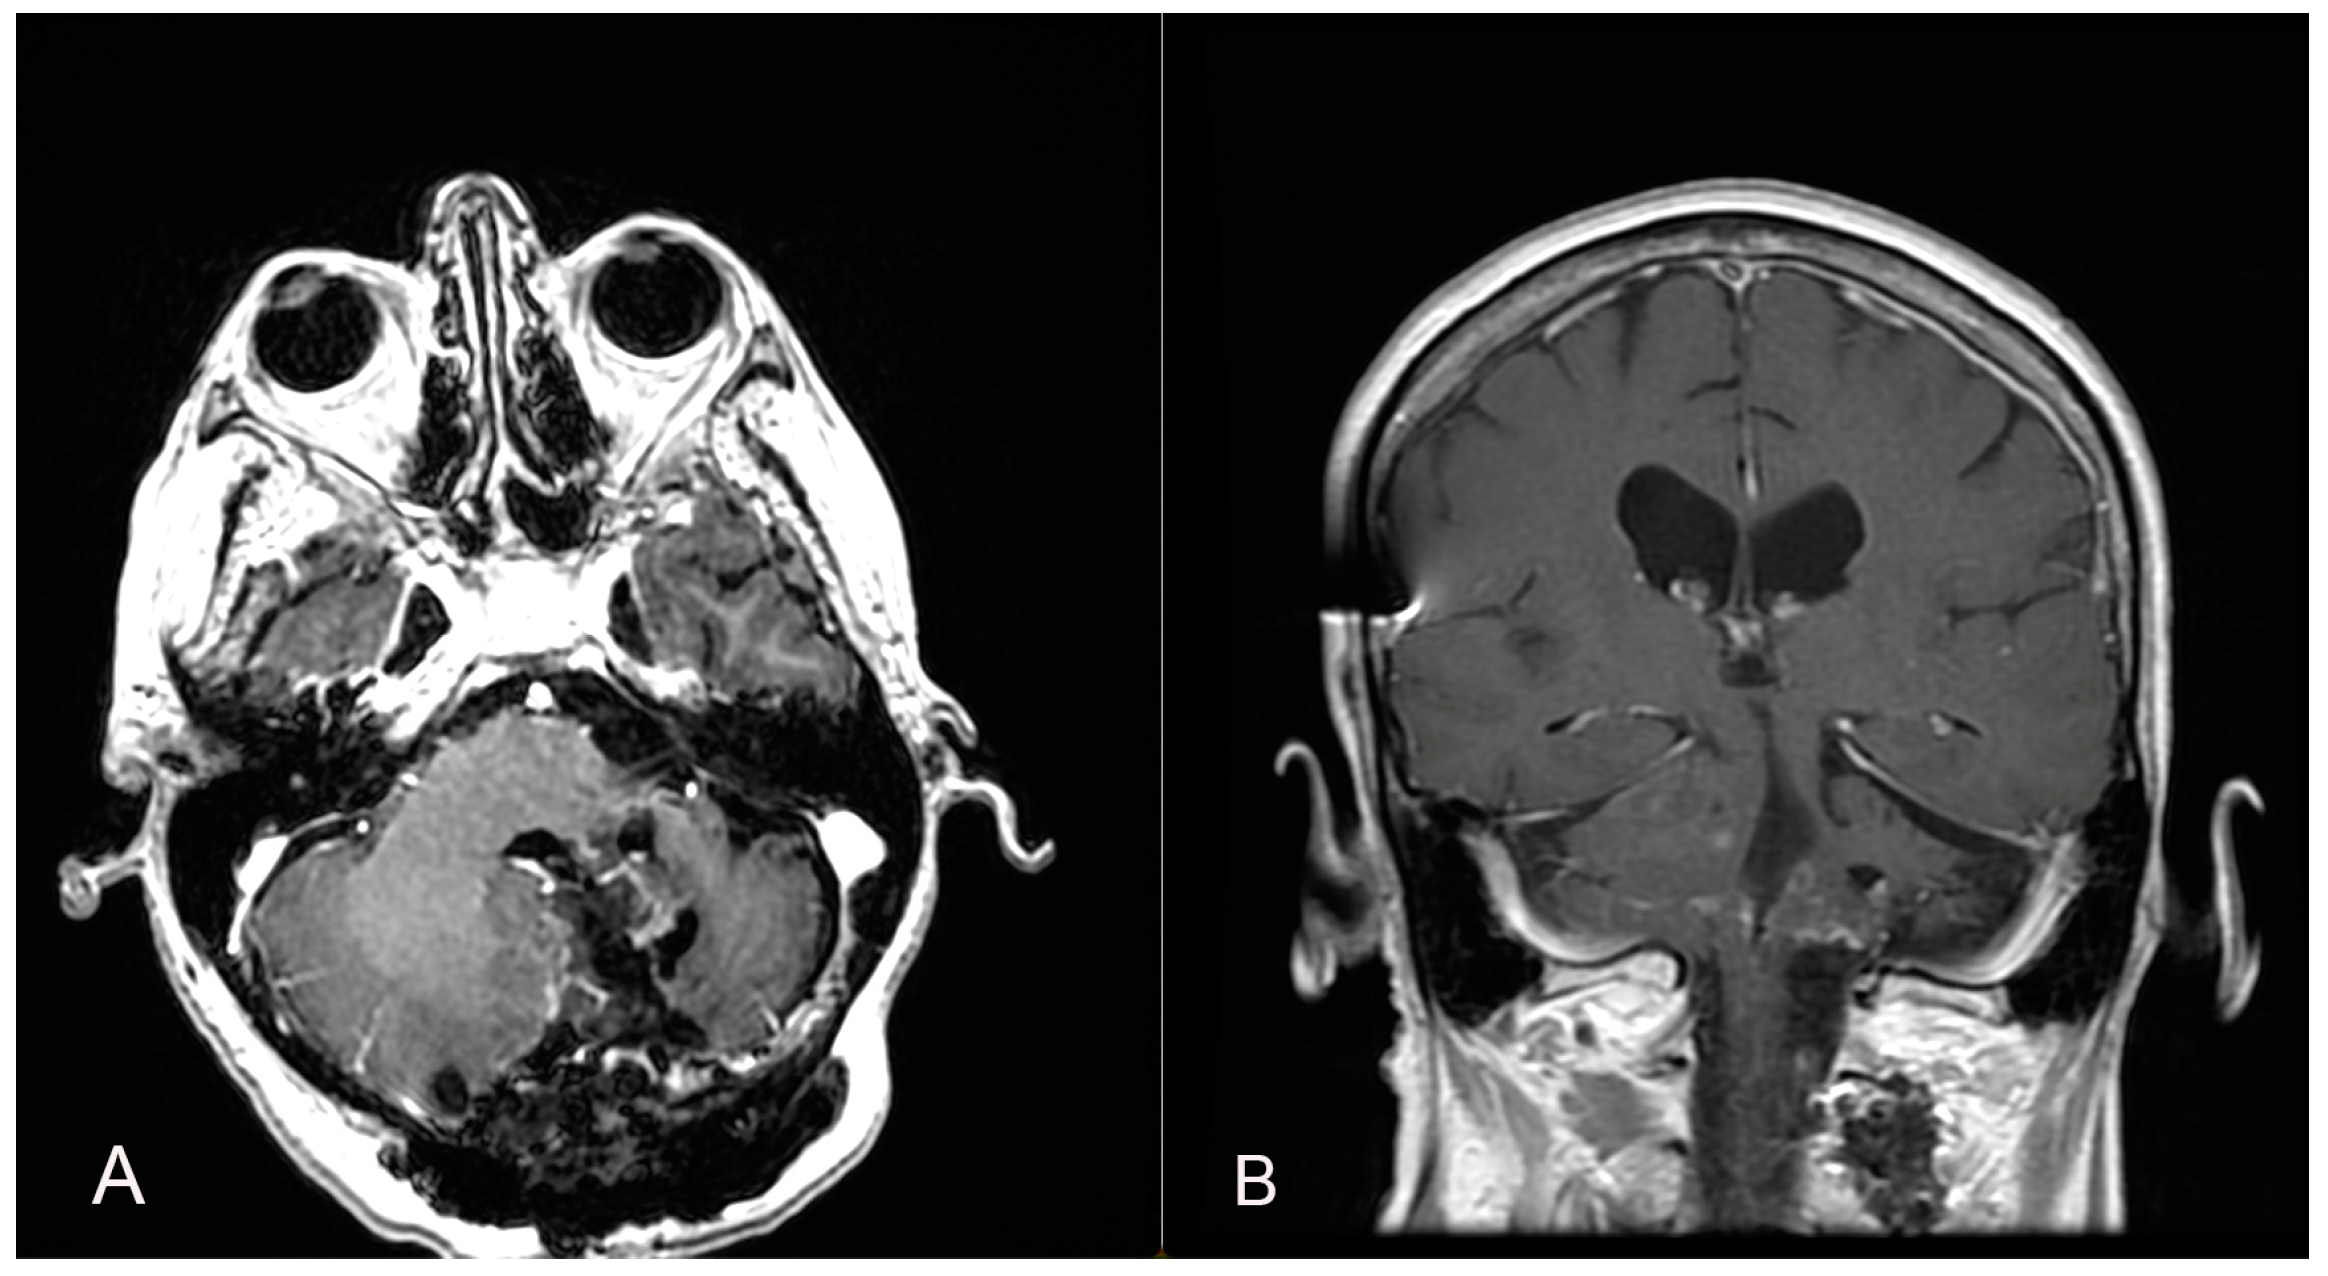

A 58-year-old woman presented with nausea, headache and gait instability. A brain contrast-enhanced magnetic resonance imaging (MRI) device documented an expansible lesion in the left cerebellar hemisphere involving the middle-lower cerebellar pedicle surrounded by perilesional edema (measures: transverse diameter: 3.2 cm; sagittal diameter: 3 cm). Compression of the IV ventricle and cerebellar tonsils herniation in the foramen magnum were present. Also, tri-ventricular obstructive hydrocephalus was present (Figure 2). The patient underwent ventricular shunt and microsurgical exeresis of the lesion via left suboccipital craniectomy (Figure 3). The histopathological examination documented a grade I glioneuronal lesion. After the first operation, the patient underwent adjuvant radiotherapy treatment with a total of 54 Gy in 27 sessions, with daily fractionation of 2 Gy/day. Clinical and radiological follow-up was then recommended.

Figure 3.

Axial (A), sagittal (B) and coronal (C) postoperative T1 contrast-enhanced brain MRI shows the left suboccipital craniectomy accomplished and the GTR exeresis of the lesion.